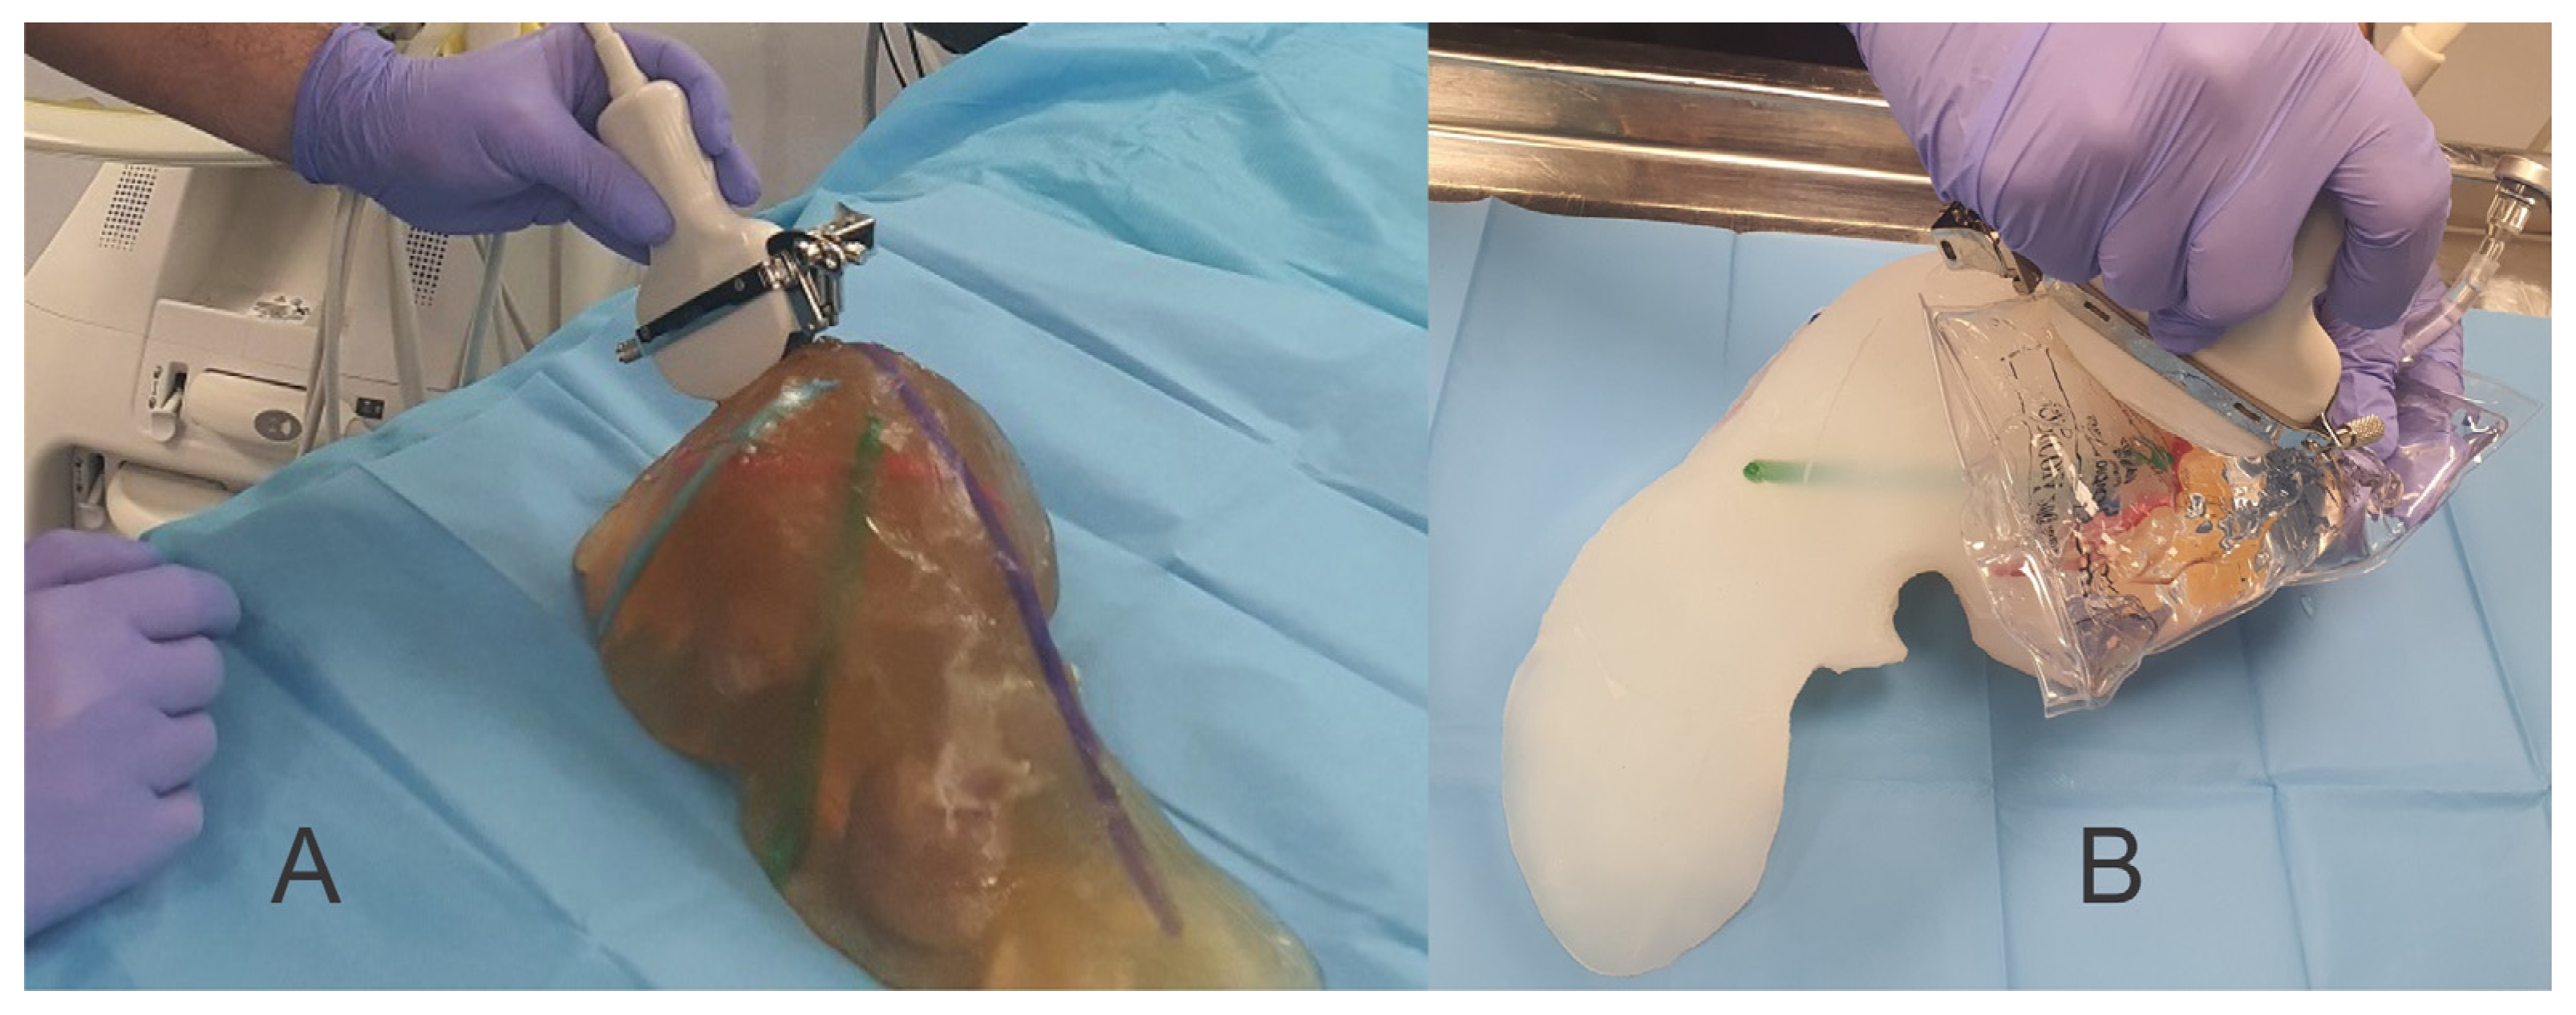

2. Materials and Methods

3. Results

4. Discussion